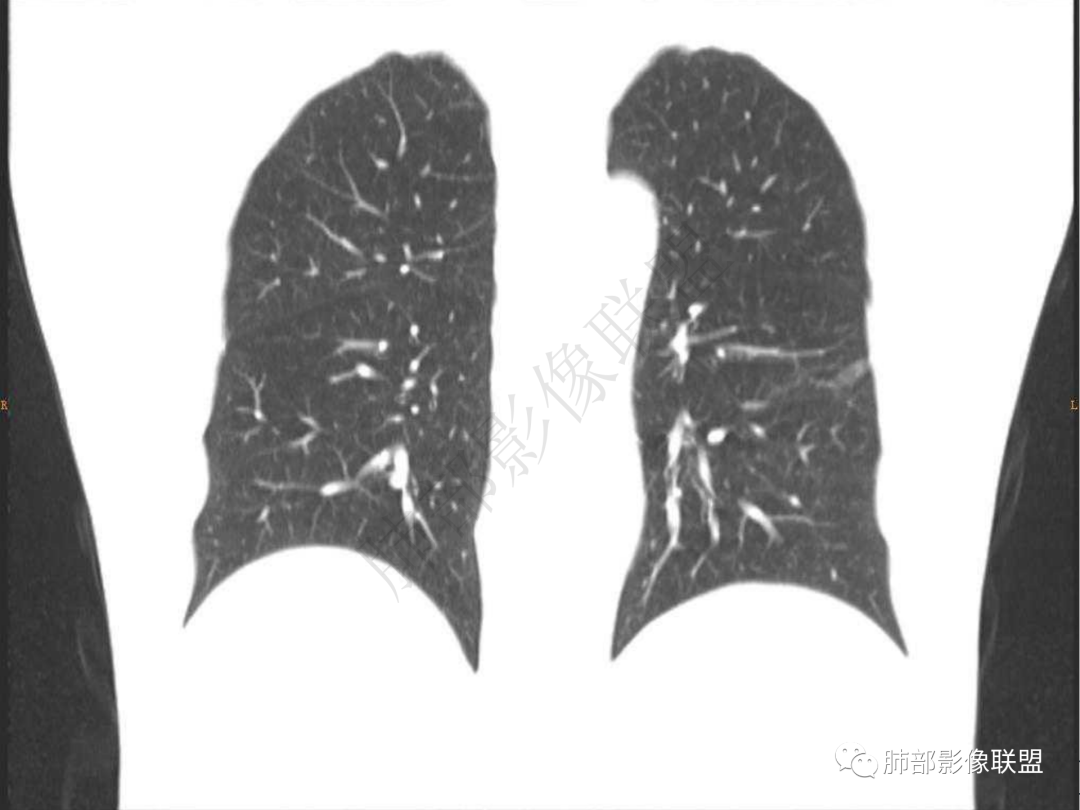

3.周边较大范围磨玻璃影,边界相当模糊,小叶增厚明显。注意叶裂另一侧、左肺舌段亦可见磨玻璃影及增厚的小叶间隔。未见明确卫星病灶。

1.病灶不够密实,没有典型分叶,收缩乏力等,支气管未见截断等,缺乏一般肿瘤性肿块特征。

2.周围磨玻璃影边界不清缺乏限制,甚至“激惹”到相邻肺叶,也许提示较明显的炎性水肿。

正如多数老师分析到的,本例病灶炎性特点比较明显。